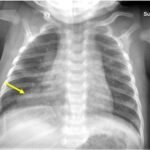

Infant tuberculosis (TB) is a rare but potentially deadly infection and difficult to diagnose, especially in infants who may present with non-specific symptoms. Here, we report a case of an United States-born term infant with community-acquired miliary TB and no confirmed TB exposure history. The patient initially presented with respiratory distress at seven weeks of life with chest radiograph showing a right lower lobe (RLL) infiltrate. After failing multiple courses of treatment for community-acquired pneumonia and developing growth faltering, the patient had imaging findings suggestive of TB infection with CNS involvement. The diagnosis of TB was confirmed by QuantiFERON and purified protein derivative (PPD). In infants who fail conventional treatment for bacterial pneumonia, the differential should be broadened to consider alternative etiologies. Additionally, brain imaging should be performed in cases of disseminated TB despite negative cerebrospinal fluid (CSF) studies since these patients are at high risk of central nervous system (CNS) involvement.